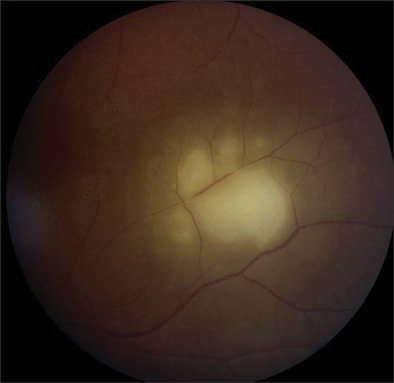

The most common presentation is posterior uveitis followed by anterior uveitis and panuveitis (Figure 6).137 Tubercular retinal vasculitis is also common and is associated with vitreous infiltrates, retinal hemorrhage, neovascularization, and neuroretinitis.138-140 Posterior involvement can be divided into 4 forms: choroidal tubercles, choroidal tuberculoma, subretinal abscess, and serpiginous-like choroiditis. The most common is multiple choroidal tubercles, which appear as small grayish nodules in the posterior pole of one or both eyes (Figure 7). These usually respond well to treatment and take up to 4 months to heal.141-143 Choroidal tuberculoma, a less common presentation in which hemorrhages and retinal folds may be seen on the tuberculoma surface,144 may be misdiagnosed as an intraocular tumor.145-147 Subretinal abscesses are yellow necrotizing granulomas that usually heal with treatment and have a good prognosis.148,149 Serpiginous-like choroiditis is a recurrent inflammation that involves the choroid and progresses to the retina, despite systemic corticosteroids and immunosuppressive agents. Additionally, the fellow eye may be affected months or years later.150,151

Figure 7. Tuberculous retinochoroiditis.